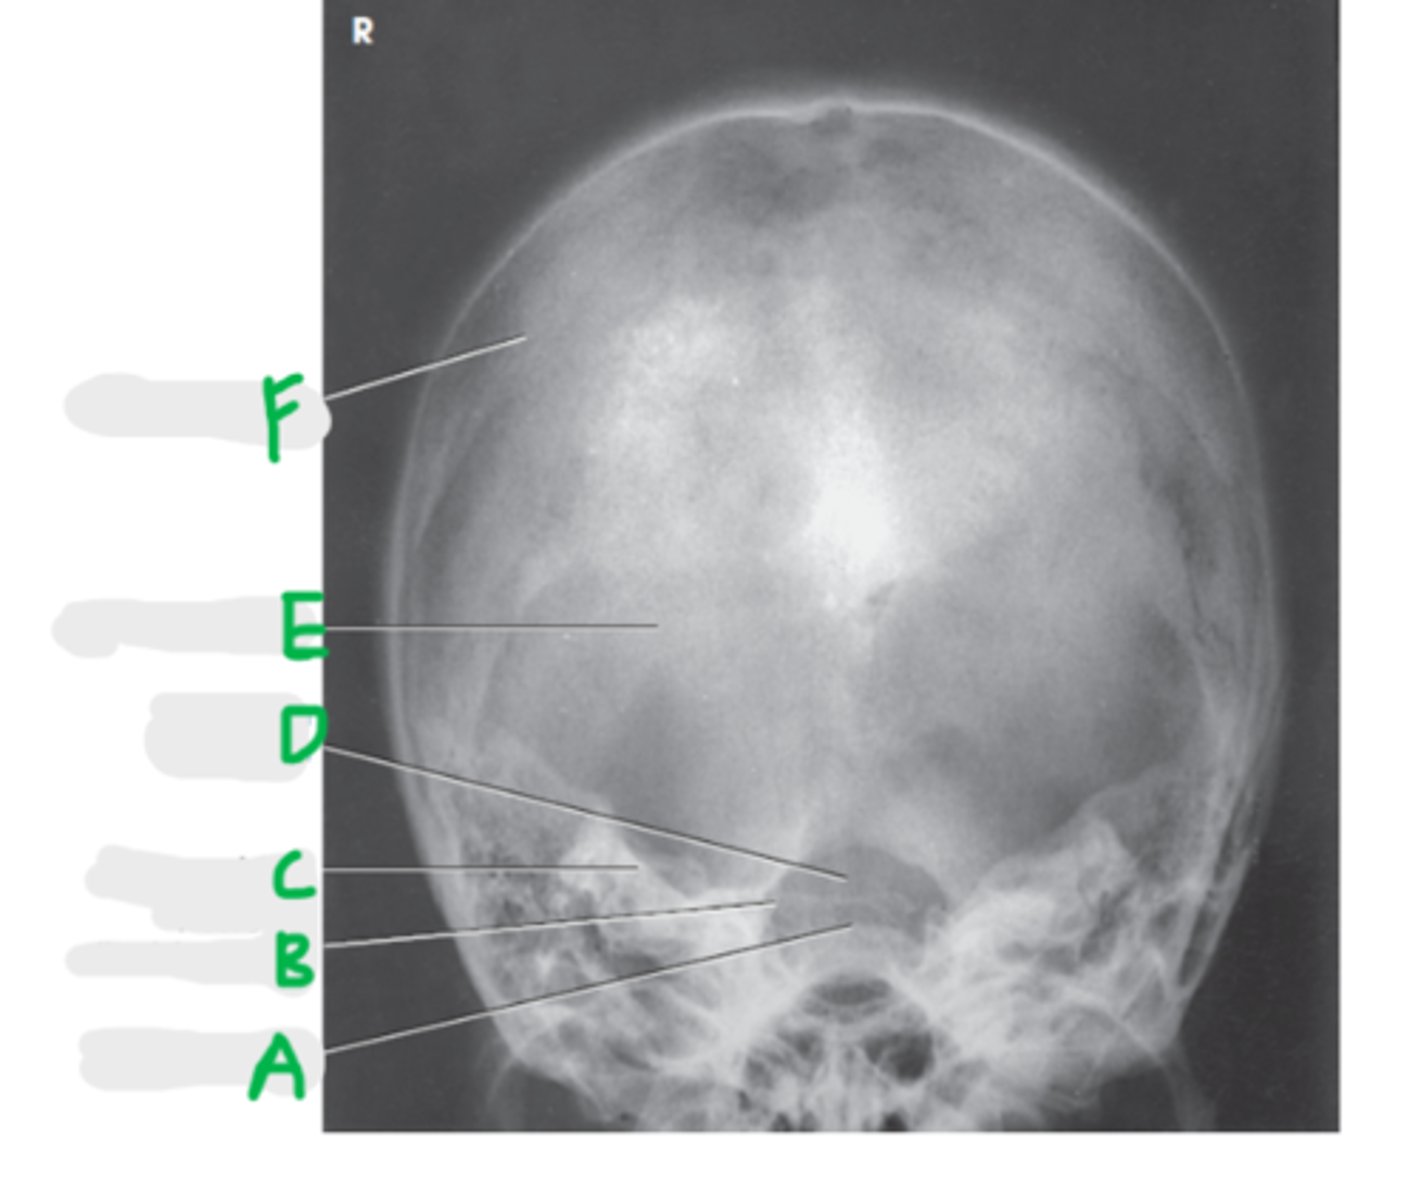

Dorsum sellae

A

Posterior clinoid process

B

Petrous ridge

C

Foramen magnum

D

Occipital bone

E

Parietal bone

F

AP axial (Townes Method)

What projection is this?

CR angled - 30 degree caudad to OML or 37 degree caudad to IOML

CR placement - 2 1/2 inches above the glabella (at hair line)

What is the CR for the AP axial (Townes)?

OML (preferred) or IOML

What line should be perpendicular to the IR?

Dorsum sellae and posterior clinoid processes projected within the foramen magnum

What is demonstrated on the AP axial (Townes)?

Equidistant from lateral borders of skull to lateral margin of foramen

Symmetric petrous ridges

How do we look for rotation on an AP axial (Townes) radiograph?